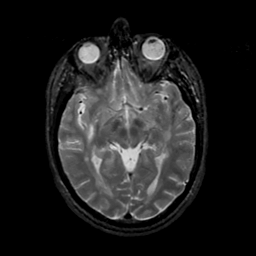

MR Study #17, July 7, 1991 -- Slice #22